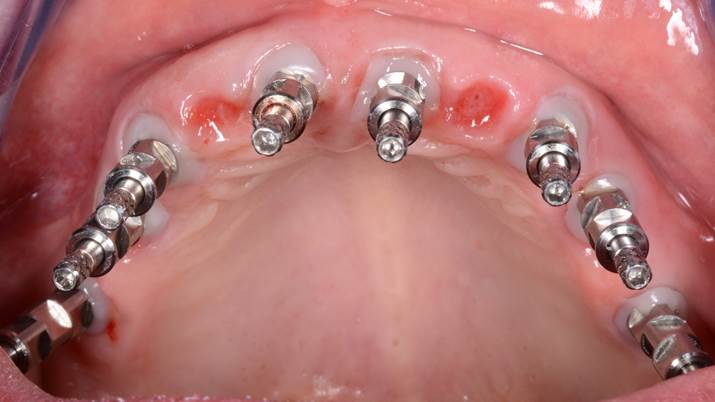

Clinical case: Extraction of all teeth in upper maxilla,

immediate implant placement, & provisionalization

- Courtesy of Dr. Iulian Filipov, Romania -

Keywords

AnyRidge, immediate placement, immediate provisionalization, maxillary fully edentulous case, initial stability, edentulous, Dr. Iulian Filipov, R2GATE, MEGA ISQ

Products:

AnyRidge implant system, Mega ISQ, R2GATE